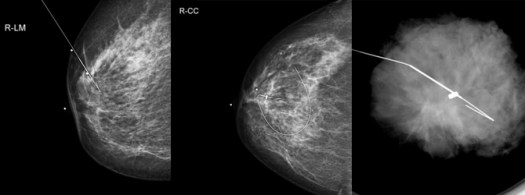

I arrived at radiology and was brought back to ultrasound. See, I had three areas of cancer. Betwen 12:30 and 1:30 on my left breast there were two areas of scattered calcifications. These show up as white dots on the mammography. In addition, I had a tiny mass that was below the line of these calcifications. Lucky me, this meant they would need two wires to define the margins left and right and one additional one to help guide my surgeon in the depth of the small mass.

On screen, calcifications look like this:

Turns out when they open you up, unless it’s an obvious mass, things are hard to see. The surgeon can’t tell where anything is in there. I guess were not color-coded like a Grey’s Anatomy book indicates. That’s the purpose of the guide wires – to define where the surgeon needs to cut to get it all out. And really, I should stop saying “wires”. In all honestly they are needles. Big, silver needles. And I understand they serve a purpose, and I am thankful for them — and actually for the radiologist who placed them. She was as precise as they come. But the experience of having them placed is nothing short of horrific.